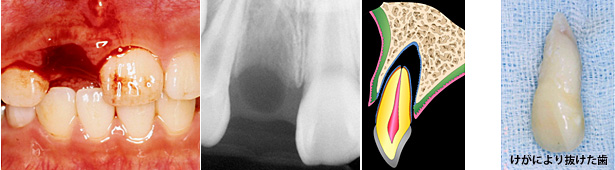

けがによる脱落歯の治療例

学校にて10歳の女の子の歯がけがで抜けました。養護の先生が抜けた歯をすぐに牛乳につけ、生徒さんを歯医者に連れて行きました。けがで抜けた歯が助かるかどうかは、歯についている歯根膜が生きているかどうかにかかっています。

歯根膜は乾燥に弱いので、すぐに以下のどれかに保存することが重要です。

抜けた歯の歯根膜を生かしておくには、身近な保存液としては牛乳が最適です。牛乳は約6時間歯根膜を生かしておくことができます。最も良い保存液は、ネオ製薬から出ているティースキーパー「ネオ」です。24時間歯根膜を生かしておくことができます。適切な保存液がない場合、口の中(唾液)に保存するのがいいと思います。そして、できるだけ早く歯医者さんに行きましょう。

再植後の経過

歯医者さんでは、検査を行った後すぐに歯を戻す治療(再植)を普通は行います。この患者さんの抜けた歯は歯根の先が閉じていましたので、再植2週間後に歯の神経(歯髄)をとる治療が行われました。8年後でも再植された歯はまったく問題がありません。